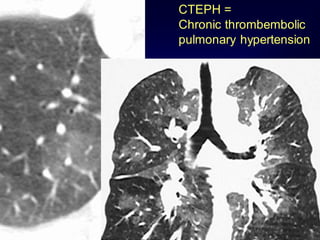

CTEPH =

Chronic thrombembolic

pulmonary hypertension

• 134.

Mosaic Perfusion Chronic pulmonaryembolism LOOK FOR Pulmonary hypertension idiopathic, cardiac disease, pulmonary disease